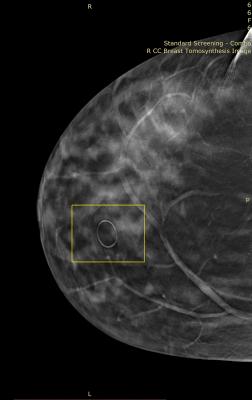

October 2, 2014 — Tested and proven for 3-D breast tomosynthesis, TomoSPOT skin markers subtly highlight areas of interest on the breast with the clearest visualization of underlying tissue detail and the least potential for “slinky” artifact compared to other mammography skin markers.

TomoSPOT skin markers for 3-D breast tomosynthesis are available in 5 distinctive shapes to identify nipples, moles, scars, palpable masses and areas of pain/concern.